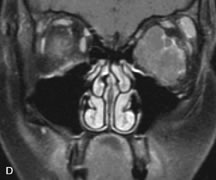

MRI is particularly helpful in the detection and characterization of subperiosteal hematomas of the orbit (Fig. 19). They are most commonly seen in the subperiosteal space of the superior orbit as well-defined masses following a traumatic injury. The signal intensity varies depending on the acute, subacute, or chronic nature of the hematoma, based on the stage of blood degradation. Fresh hemorrhages are hypointense on T1-weighted images and hyperintense on T2 images. Hematomas that are 1 to 7 days old are hypointense on both T1- and T2-weighted images. T1-weighted images of hematomas more than a week old are hyperintense due to the oxidation of deoxyhemoglobin to methemoglobin, whereas the T2 images remain hypointense.63

Fig. 19. A. T1- and (B) T2-weighted MR scans demonstrate a large acute subperiosteal hematoma (H) that lies between the cortical bone of the orbital roof and the inferiorly displaced periorthira (double arrow). The extracopal fat (arrow) and levator muscle are displaced inferiorly.